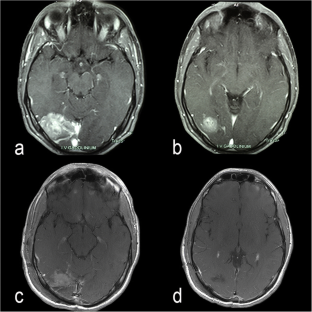

Fig. 2